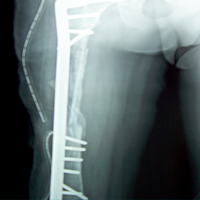

Case:5 Ewing sarcoma with implant failure

Orthopedic Oncology Doctor In Ahmedabad

Breakage of Nail

Sports Injuries Doctor

Refixation with Angle Bladed Plate and Sever Graft

Spine Best doctor

Ewing's Post Nailing and Bone Grafting

Best Trauma Surgeon in Ahmedbad

3 Months Post -Op

Joint Replacement

6 Months Post-Op